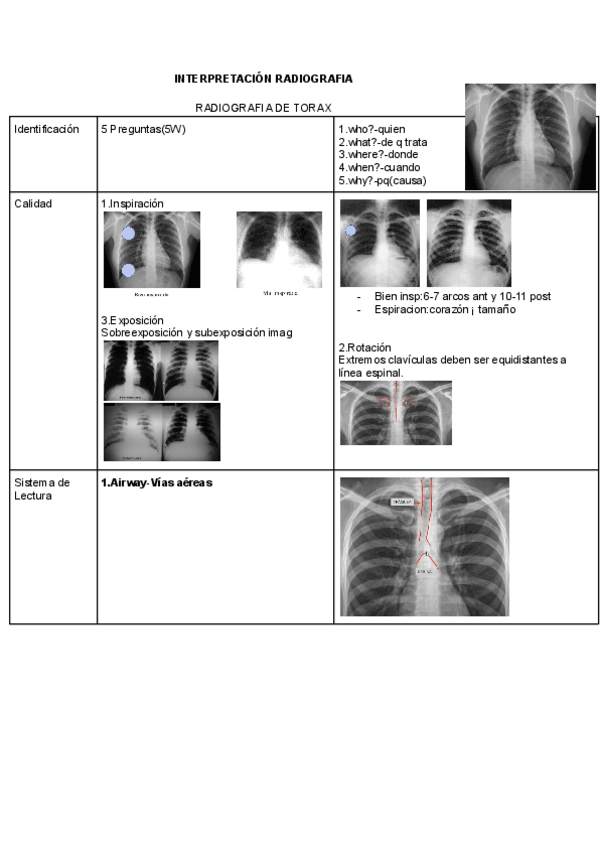

resumen-tema-rayos.pdf